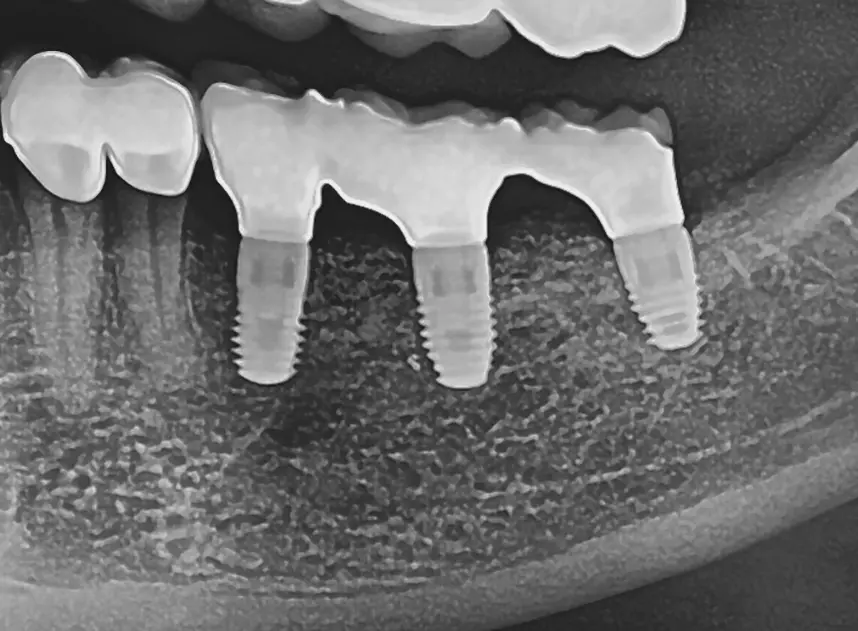

Vor dem abschließenden spannungsfreien und speicheldichten Wundverschluss (Abb. 10) erfolgte die Abdeckung der Implantate und des Knochenaufbaus mit einer Kollagen- (Geistlich Bio-Gide®, Geistlich Biomaterials) und PRF-Membran (Abb. 9). Das postoperative Röntgenbild (Abb. 11) zeigt die entsprechend der Planung gesetzten Implantate mit aufgeschraubten Heilungskappen. Zehn Tage postoperativ konnten die Fäden entfernt werden. Die Wunde zeigte sich in guter, völlig reizfreier Abheilung (Abb. 12).

Nach 6 Monaten Einheilzeit wurde die Gitterentfernung mit gleichzeitiger Implantation durchgeführt. Nach Vorbereiten der Patientin und entsprechender Lokalanästhesie wurde eine marginale, entlang an Zahn 34 und der vorhandenen Narbe krestale leicht linguale Schnittführung gewählt. Zur Darstellung des Gitters wurde ein vestibulärer und lingualer Mukoperiostlappen präpariert. Das Gitter zeigte sich regelrecht eingeheilt und zum Teil sogar knöchern bedeckt (Abb. 28). Zur Entfernung des Gitters wurde dieses an der mittleren Sollbruchstelle aufgebrochen und der linguale und vestibuläre Anteil getrennt entfernt (Abb. 29a und b). Anschließend wurde das Implantatlager vorgebohrt und entsprechend dem Bohrprotokoll des Herstellers aufbereitet (Abb. 30). Der Planung folgend wurden dann drei Implantate (Bego SC) regio 35 mit 4,1 x 8,5 mm, regio 36 mit 4,5 x 8,5 mm und regio 37 mit 4,5 x 7mm gesetzt (Abb. 31). Für eine Nachkorrektur der Knochenkontur um die gesetzten Implantate wurde nochmals DBBM eingebracht, mit einer Kollagenmembran (Geistlich Bio-Gide) und PRF abgedeckt und mit einer spannungsfreien Naht verschlossen (Abb. 32 und 33). Das postoperative Röntgenbild zeigt die drei gesetzten Implantate (BEGO SC) an den jeweils vorher digital geplanten Implantatpositionen (Abb. 34).

Die Freilegungsoperation fand nach etwa vier Monaten Einheilzeit statt. Die Implantate zeigten sich regelrecht eingeheilt und gedeckt von einer vitalen Knochenschicht (Abb. 35 und 36). Zur Ausformung der Gingiva wurden die Implantate regio 35 mit einem 4,1 x 3 mm und regio 36 und 37 mit einem 4,5 x 5 mm Gingivaformer versorgt. Zur Gerüsteinprobe (Dentalwerk Nürnberg) drei Wochen nach Eingliederung (Abb. 38) zeigen sich gesunde, reizfreie Schleimhautverhältnisse mit einer ausreichenden Schleimhautdicke (Abb. 37). Abschließend werden die Implantate prothetisch mit einem vollkeramischen Kronenblock (Dentalwerk Nürnberg) drei Wochen nach Freilegung versorgt (Abb. 39a und b). Nach Eingliederung der Prothetik wurde ein abschließendes Kontrollröntgen (Abb. 40) angefertigt, das suffizient eingeheilte Implantate mit mehr als ausreichendem Knochenangebot zeigt.